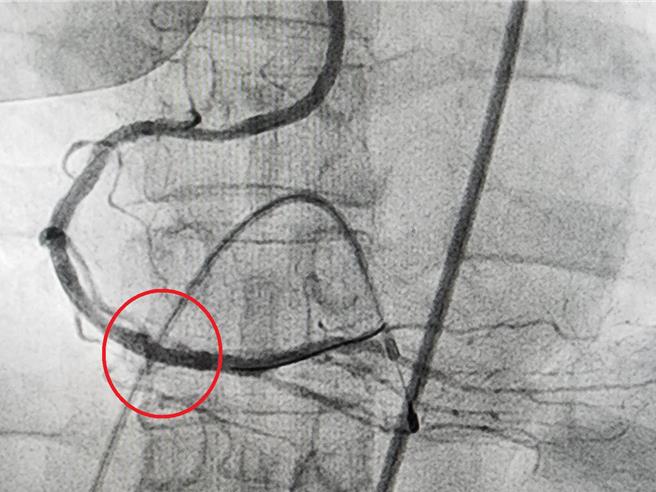

邱女士在接受治疗后,原本钙化严重的病况获得良好的改善(红圈处)。(大千医院提供/吕丽甄苗栗传真)

邱女士在接受心导管冠状动脉摄影检查后,发现右冠状动脉钙化严重,并且存在无法通过的狭窄病灶。儘管经过一个月的药物治疗,她的症状依然未见改善,最终转向心导管冠状动脉旋磨治疗术进行处理。这项技术搭配血管内超音波,成功去除了钙化病灶,并顺利置放支架。

这项技术适用于传统气球扩张术难以处理的严重钙化病变,能有效改善血管狭窄的情况,并为后续支架置放创造更好的条件。它还能降低血管再狭窄的风险,为患者提供更长期的治疗效果。